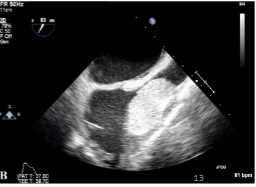

Rhabdomyoma

What is seen in this TTE?

<p>What is seen in this TTE?</p>